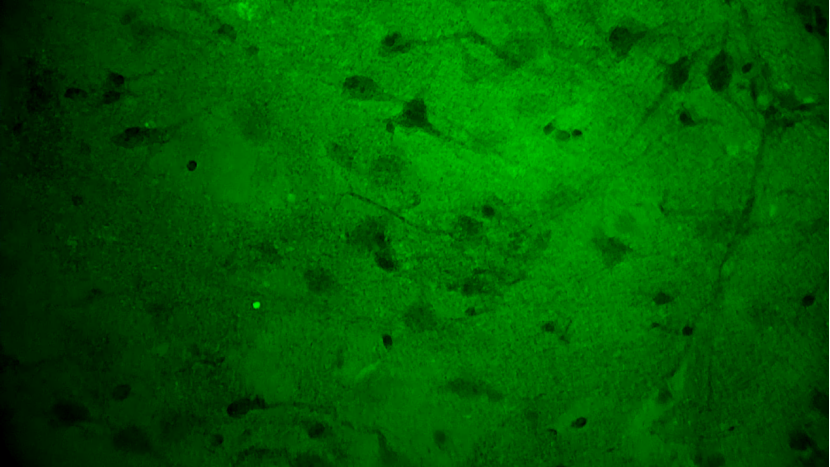

手術(shù)切緣處發(fā)現(xiàn)的正常腦白質(zhì):細胞核形態(tài)正常,密度低且分布均勻

神經(jīng)元細胞:神經(jīng)纖維束清晰、密度低